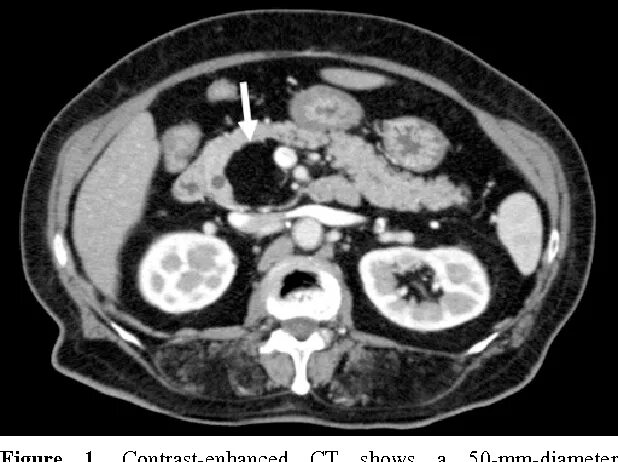

Диффузные изменения паренхимы поджелудочной по типу липоматоза